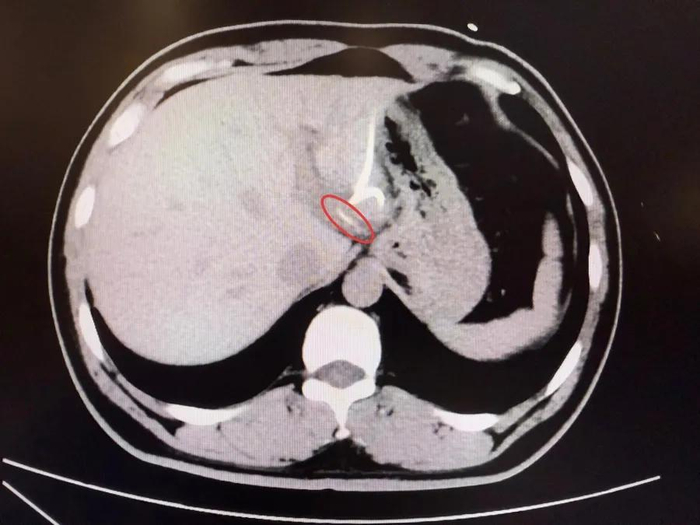

Mãi đến khi chụp CT, các bác sĩ mới phát hiện một vật thể dài, nhọn trong gan trái, gần vùng nối với dạ dày, hình dạng giống hệt… một chiếc xương cá! Hóa ra, chiếc xương này đã xuyên qua thành dạ dày, “chui” thẳng vào gan, gây nhiễm trùng và tạo ổ mủ lớn.

Người đàn ông 37 tuổi suýt mất nửa lá gan vì ăn cá- Ảnh 1.

Sau hơn 3 tiếng đồng hồ, các bác sĩ đã tìm thấy chiếc xương cá dài 3,5cm, sắc nhọn như kim, cắm sâu trong gan trái. Sau ca mổ, anh Lý hồi phục tốt, nhiệt độ cơ thể trở lại bình thường, ổ áp xe dần tiêu biến và quan trọng hơn cả, anh giữ được nguyên vẹn lá gan của mình .